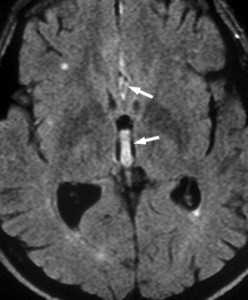

МРТ головного мозга. Аксиальная МРТ типа FLAIR. Аневризма и САК, внутрижелудочковое кровоизлияние.

Субарахноидальное кровоизлияние (САК) - это кровоизлияние между арахноидальной и мягкой мозговыми оболочками. Эпидемиология САК отличается в разных странах, в России около 6 на 100 тысяч населения. Самой частой причиной САК является травма, затем разрыв мешотчатой аневризмы (85% от нетравматических спонтанных кровоизлияний). На оставшиеся 15% нетравматических кровоизлияний приходятся доброкачественное перимезэнцефальное кровоизлияние неясной этиологии и разрыв вен. Смертность от САК очень высокая, и зависит от массивности и расположения кровоизлияния.

При неврологическом осмотре выявляются менингеальные знаки - часто единственный признак САК. Ксантохромия СМЖ появляется через 12 и более часов после САК и может быть только методом позднего его подтверждения. Предлагаются разные подходы к лучевой диагностике САК. В первые сутки предпочтительна МРТ, так как кровь уже может быть видна на Т2-МРТ градиентного типа или FLAIR. В более поздние сроки, до 3-5 дня предпочтительнее КТ. Затем опять МРТ, которая чувствительнее КТ в подострую и хроническую фазы кровоизлияния.

Субарахноидальное кровоизлияние опасно вазоспазмом, который наблюдается на 5-7 сутки. Сам спазм хорошо определяется при дуплексном сканировании. При МРТ головного мозга можно выявить ранние признаки ишемического инсульта.

МРТ головного мозга. Диффузионно-взвешенная МРТ последовательность. ОНМК в острой стадии вследствие вазоспазма.